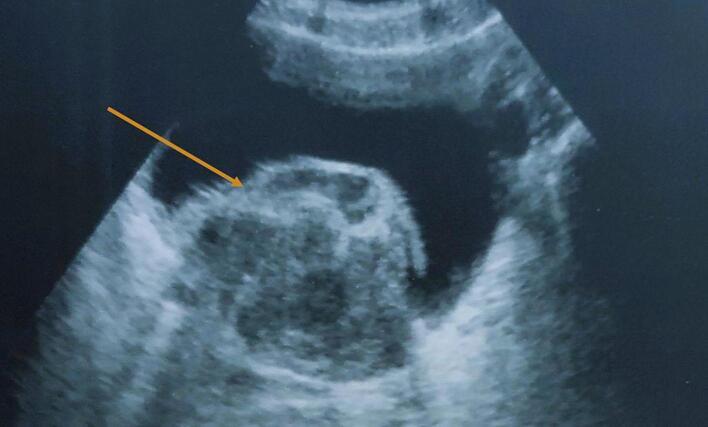

An 81-year-old male with a 30-pack-year smoking history presented with clotting hematuria and acute renal failure. Imaging revealed a large bladder mass causing bilateral ureteral obstruction. Transurethral resection and immunohistochemical analysis confirmed an SFT. The patient underwent cystoprostatectomy with Bricker diversion, achieving full recovery.

一名有30年吸烟史、81岁的男性患者,出现凝血性血尿和急性肾衰竭。影像学检查显示膀胱有一个大肿块,导致双侧输尿管梗阻。经尿道切除术及免疫组化分析确诊为SFT。患者接受了膀胱前列腺切除术及Bricker尿流改道术,实现了完全康复。